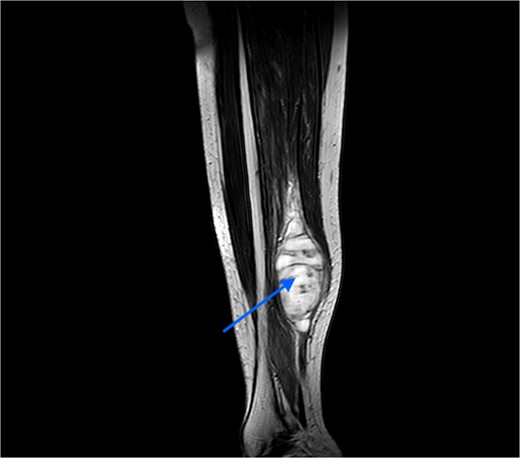

An MRI was done, which suggested a multi-lobulated spindle-shaped mass (Fig. 6).

MRI image taken in coronal view, which was suggestive of a spindle-shaped mass lesion (indicated by arrow) located in the posterior compartment of the leg.